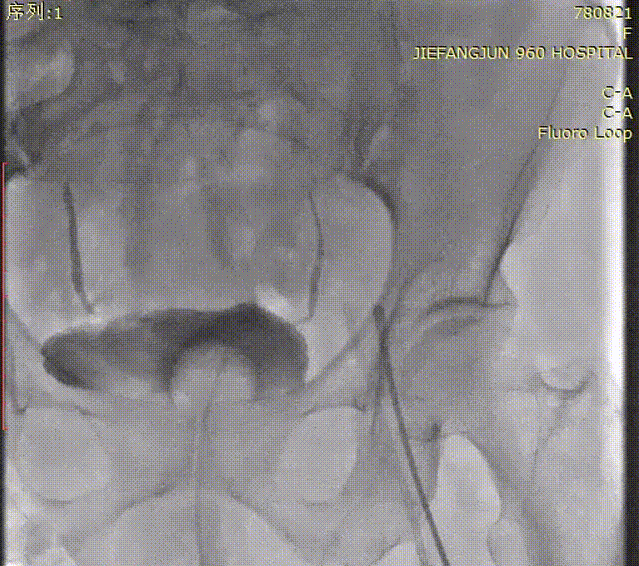

瓣膜释放后造影

术后入路检查

术后造影提示,瓣膜位置、膨胀形态良好。手术过程流畅,瓣膜功能即刻达标,患者术后恢复顺利。